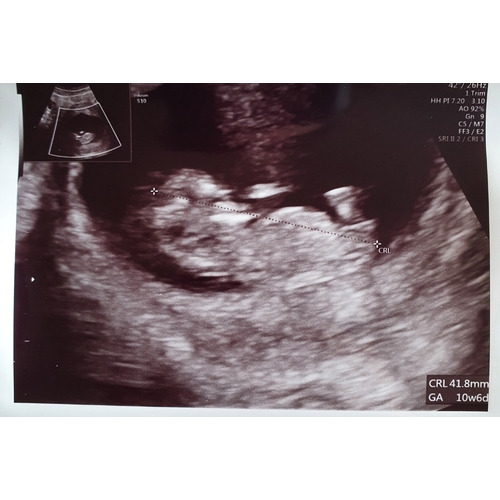

Julie hebben zulke mooie echo’s ik heb altijd echo’s waar ik zelf niet eens de beentjes kan zien 🤦🏽‍♀️ ze zeggen toch als het omhoog is is het een jongetje en laag een meisje. Die van jou lijkt naar beneden of niet ?

Voor zover ik het goed kan zien zou ik denken een meisje. Heb je zelf een gevoel er ook bij? Ik heb heel sterk het gevoel dat ik een jongetje ga krijgen dus ben heel benieuwd naar de 12 weken echo

Als je voor de 12 weken de nub-theorie toepast, verandert de hoek van nub nog teveel en is de uitslag onbetrouwbaar.

Ik heb het gevoel dat het een meisje is. Maar een jongen is ook helemaal goed🥰 maakt niet uit wat het is/wordt. Ben gewoon nieuwsgierig 😄

Aan de stand van de nub zou ik denken een meisje. Bij zowel mijn zoontje als bij mijn dochter klopte de nub theorie.